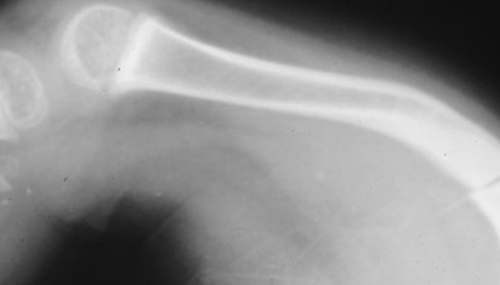

1、骨脆性增加,轻微的损伤即可引起骨折,严重的病人表现为自发性骨折。先天型者在出生时即有多处骨折。骨折大多为青枝型,移位少,疼痛轻,愈合快,依靠骨膜下成骨完成,因而常不被注意而造成畸形连接。长骨及肋骨为好发部位。多次骨折所造成的畸形又进一步减少了骨的长度。青春期过后,骨折趋势逐渐减少。